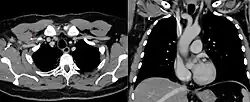

Diagnostik

Die Sonographie mit Farbdoppler ist heute die Methode der Wahl zur Diagnosestellung. Als ältere Methode steht die Armvenenphlebografie zur Verfügung. Dabei wird Kontrastmittel über eine Armvene gespritzt und der Ablauf über die Venen zum Herzen unter Durchleuchtung beobachtet und als Röntgenbild dokumentiert.